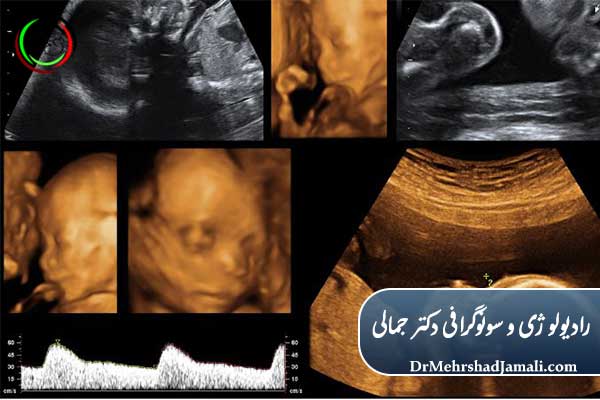

آنومالی اسکن یکی از مهمترین سونوگرافیهای بارداری است که بین هفته ۱۸ تا ۲۲ انجام میشود. آشنایی با بهترین زمان، هزینه و بهترین مرکز در تهران.

بارداری یکی از حساسترین و مهمترین دوران زندگی هر مادر است. در این دوره، تشخیص زودهنگام هرگونه مشکل یا ناهنجاری جنین میتواند تاثیر مستقیم بر سلامت مادر و کودک داشته باشد. یکی از مهمترین ابزارهای تشخیصی در این زمینه، سونوگرافی آنومالی یا همان آنومالی اسکن است. این اسکن به پزشکان کمک میکند تا رشد و تکامل جنین را بهطور دقیق بررسی کنند و ناهنجاریهای احتمالی را شناسایی کنند.

آنومالی اسکن به عنوان یک سونوگرافی سطح دو (Level 2 Ultrasound) شناخته میشود و نسبت به سونوگرافی معمولی جزئیات بیشتری از بدن جنین ارائه میدهد. بسیاری از والدین با شنیدن نام آنومالی اسکن ممکن است دچار نگرانی شوند، اما باید بدانید که این روش کاملاً ایمن و غیرتهاجمی است.

آنومالی اسکن یک سونوگرافی تخصصی است که در دوران بارداری انجام میشود تا ساختارهای بدن جنین به طور کامل بررسی شود. این اسکن میتواند مشکلات قلبی، مغزی، کلیوی، ستون فقرات و دیگر اندامهای داخلی جنین را تشخیص دهد.

در این سونوگرافی، پزشک علاوه بر مشاهده جنین، جفت، مایع آمنیوتیک و بند ناف را نیز ارزیابی میکند. هدف اصلی آنومالی اسکن، شناسایی ناهنجاریهای مادرزادی است تا در صورت نیاز، مراقبتهای تخصصی و برنامهریزی پزشکی انجام شود.